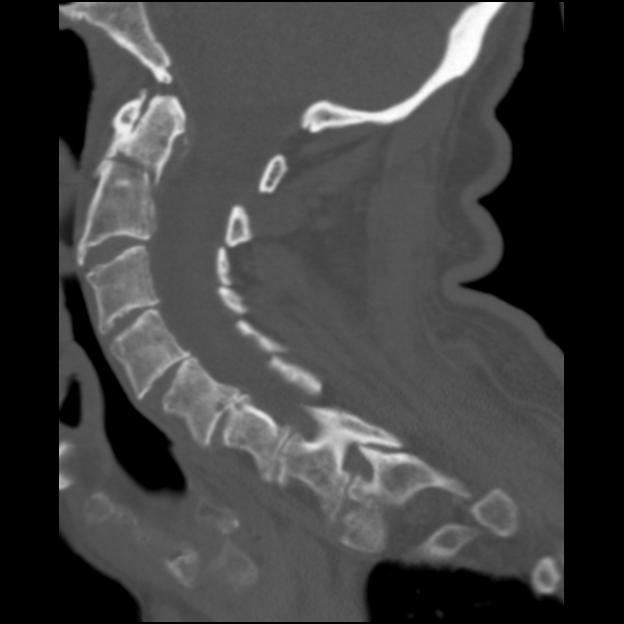

Dens Fx, Sagittal Alignment, and Impact Professionally Integrated Care What Is A Dens Fx Odontoid fractures are relatively common fractures of the c2 (axis) dens that can be seen in low energy falls in elderly patients. Odontoid process fracture, also known as a peg or dens fracture, occurs where there is a fracture through the odontoid process. We will briefly explain what a den's fracture is, how an odontoid fracture is diagnosed, different ways. What Is A Dens Fx.